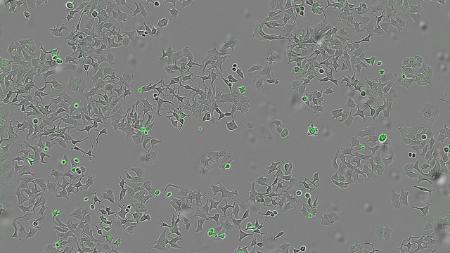

به گزارش انتخاب به نقل از یورونیوز، بنا بر این مطالعه که در نشریهٔ Cell Death Discovery منتشر شده است، این پروتئین امیدبخش که HapA نام دارد، توسط باکتری عامل بیماریِ «وبا» ترشح میشود. پژوهشگران این مکانیسم جدید را در سلولهای غدههای پستانی، رودهٔ بزرگ و پانکراس مورد آزمایش قرار دادهاند.

تیم پژوهشی با انجام آزمایشهایی روی گونههای جهشیافتهٔ وبا که فاقد این پروتئین بودند همچنین روی نوع دیگری از باکتری که بهصورت ژنتیکی طوری تغییر یافته بود که فقط HapA تولید کند، نشان داد که تنها در حضور HapA، زندهمانی سلولهای توموری کاهش مییابد.

آنها همچنین بررسی کردند که آیا HapA در برابر انواع مختلف غدههای سرطانی مؤثر است یا نه، و برای این کار مایعی حاوی تمام پروتئینهای ترشحشده توسط باکتری را روی ردههای سلولی سرطان پستان، روده و پانکراس اعمال کردند.